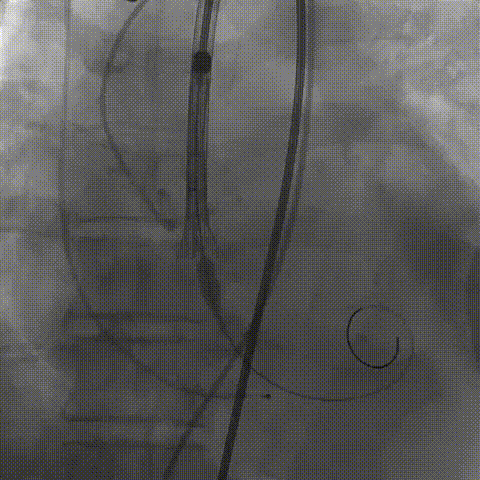

瓣膜(AV29)完全脱钩释放后23mm球囊充分后扩,冠脉灌注良好

最后造影

术后血流动力学

瓣膜工作状态良好,极微量瓣周漏,血流动力学有效改善